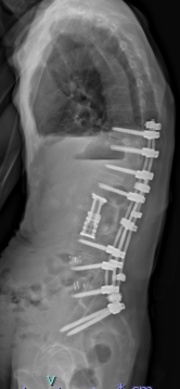

高度腰曲がり・脊柱後弯症・成人脊柱変形の患者さんです。難治性の腰痛、バランス不良により歩くことも困難な状態でした。

腰椎側方経路椎体間固定術と後方矯正固定術を2回に分けて行い、生理的な胸椎後弯・腰仙椎前弯・骨盤前傾が復元されました。腰痛・歩行障害は改善し、近所のスーパーへ歩いて買い物にも行けるようになり、台所の仕事も痛みなく出来るようになりました。